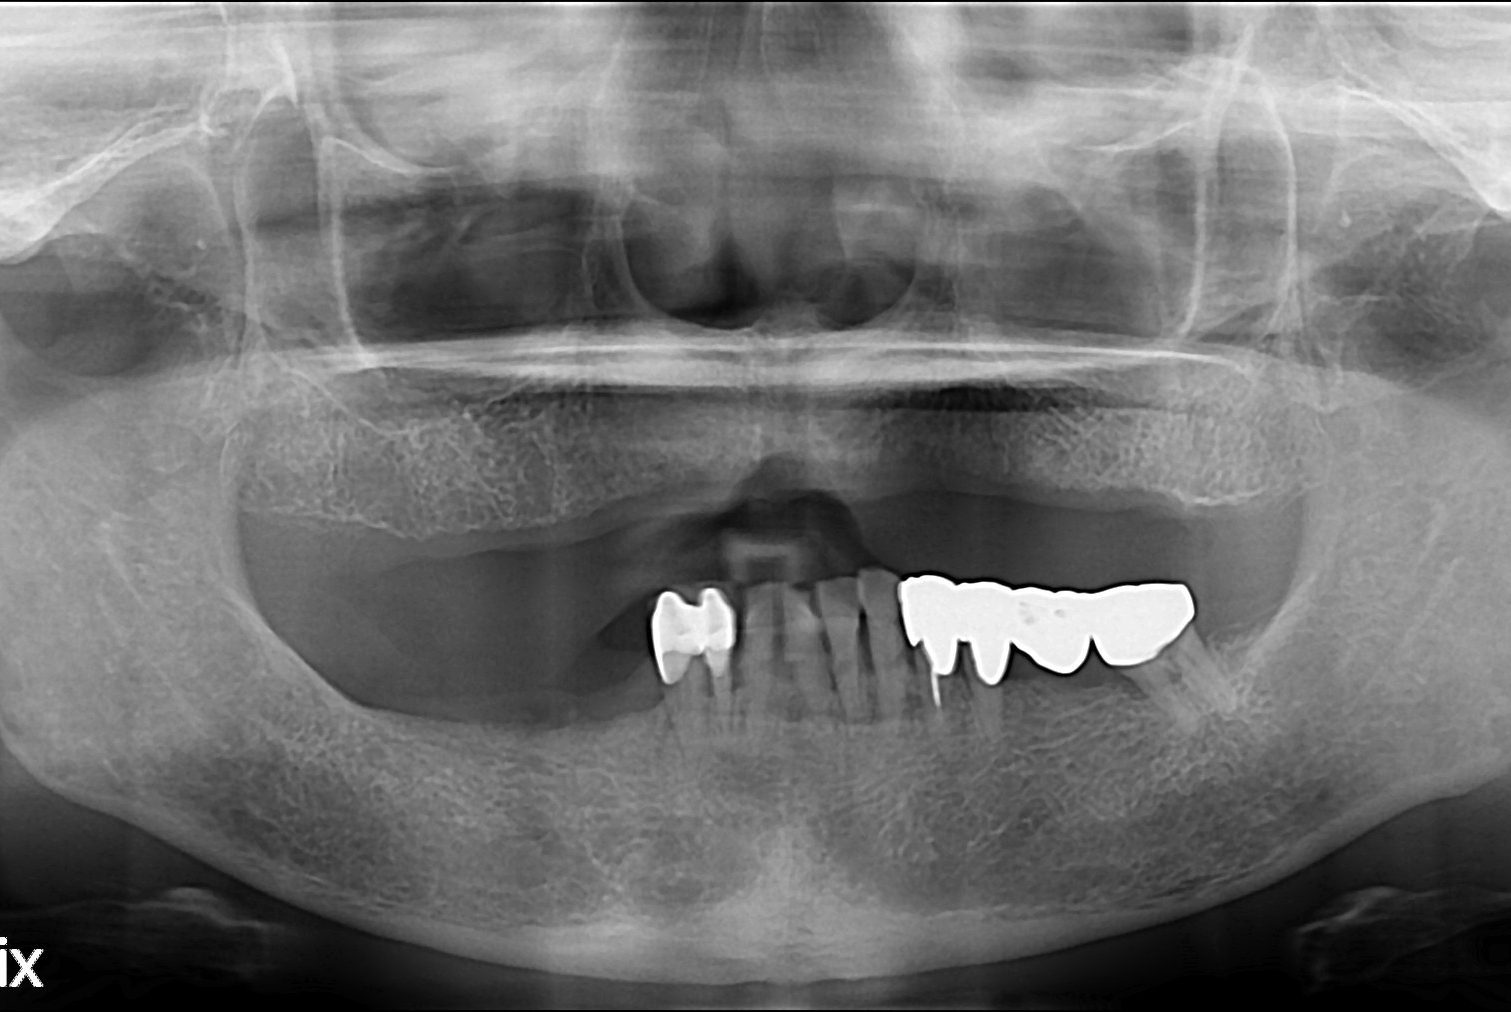

치료전 : 2016-01-29

이경순 후.jpg